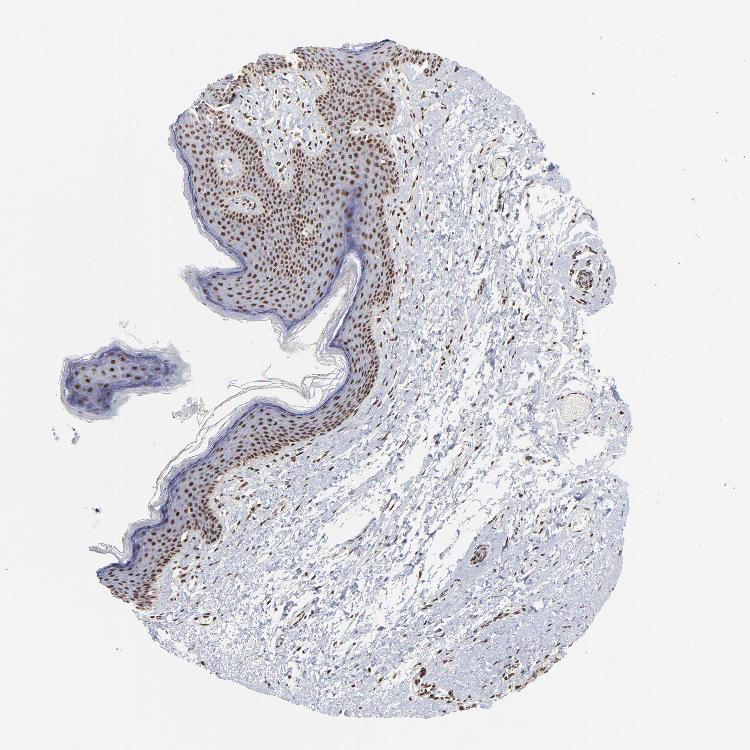

SKIN 1 - Antibody stainingi

Antibody staining in the annotated cell types in the current human tissue is reported as not detected, low, medium, or high, based on conventional immunohistochemistry profiling in selected tissues. This score is based on the combination of the staining intensity and fraction of stained cells.

Each image is clickable and will lead to virtual microscopy that enables deeper exploration of all samples and also displays staining intensity scores, fraction scores and subcellular localization as well as patient and tissue information for each sample.

Antibody HPA001634

Langerhans High

Fibroblasts High

Keratinocytes High

Melanocytes High

SKIN 2 - Antibody stainingi

Epidermal cells High